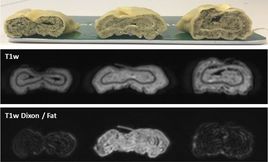

Maultaschen mit unterschiedlicher Füllung: Spinat (links), Schweinefleisch (Mitte), Rindfleisch (rechts)

Erste MR-Bildgebung am ersten 1,5 T MR-Linac in Tübingen

Yesterday, when the CE mark for the Unity was announced, the team at Radiation Oncology University of Tübingen has taken the first images. The installation in Tübingen is the first commercially available Unity system in the world. The program of MR-guided Radiation Oncology is funded by the German Research Council (DFG), the Medical Faculty and the University Hospital Tübingen.  The team in Tübingen will start to image the first patients today and expect the first treatments within the next few weeks.